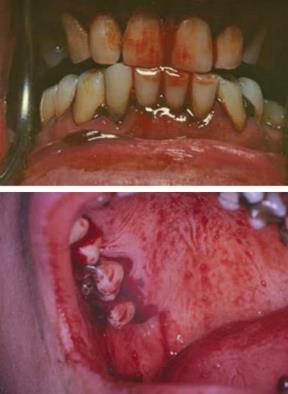

Ha a keringésben a thrombocytaszám vagy -funkció csökken, a szövetekben spontán vérzések alakulhatnak ki. Korai szakban ezt jelezhetik petechiák, bevérzések a szájnyálkahártyán és ez az immun-thrombocytopenia korai jele is. A különböző típusú leukaemiákban a thrombocytaszám és -funkció is jelentősen csökken a nyálkahártyán, és a bőrön is vérzések alakulhatnak ki, ez korai riasztó jel. Indokolatlan vérzés esetén azonnal kérjünk laborvizsgálatot, mert a fogászati beavatkozás akár fatális kimenetelű is lehet az ilyen betegeknél (15.8. ábra).

15.8. ábra. Középkorú férfi beteg spontán vérző gingivája akut thrombocytopeniában

(Gera I felvétele)